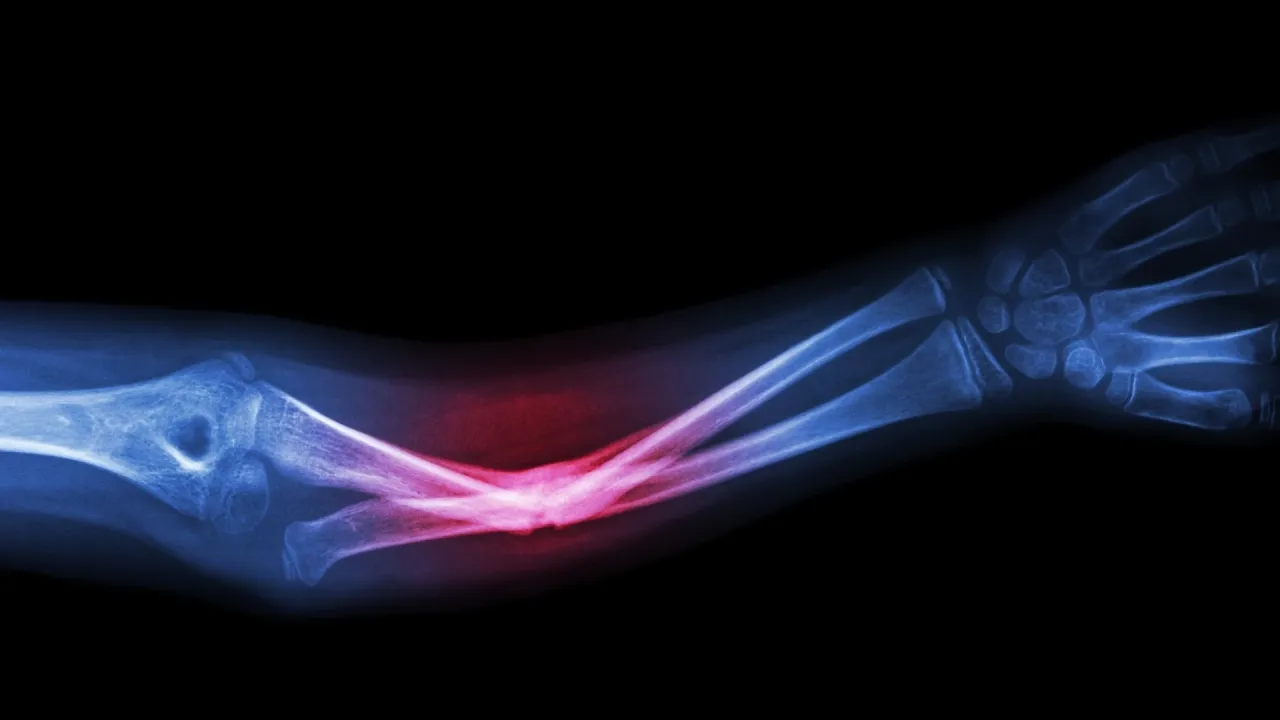

خبرني - يُعتزم استخدام الذكاء الاصطناعي في المستشفيات لاكتشاف الكسور والخلوع وتقديم علاج أسرع، ضمن تجربة جديدة في إنجلترا.

وأوضحت المؤسسة أن برنامج الذكاء الاصطناعي سيُستخدم كأداة إضافية لمساعدة الأطباء في تشخيصهم.

وقال جيك بايتس، وهو أخصائي ممارس ومتخصص في الأشعة: "تقوم الفكرة على أنه إلى جانب صور الأشعة التقليدية، سيتضمن سجلّ المريض نسخة معالجة فورياً بالذكاء الاصطناعي تشير إلى أي مشكلات محتملة قد يرغب الطبيب في فحصها بشكل أدق".